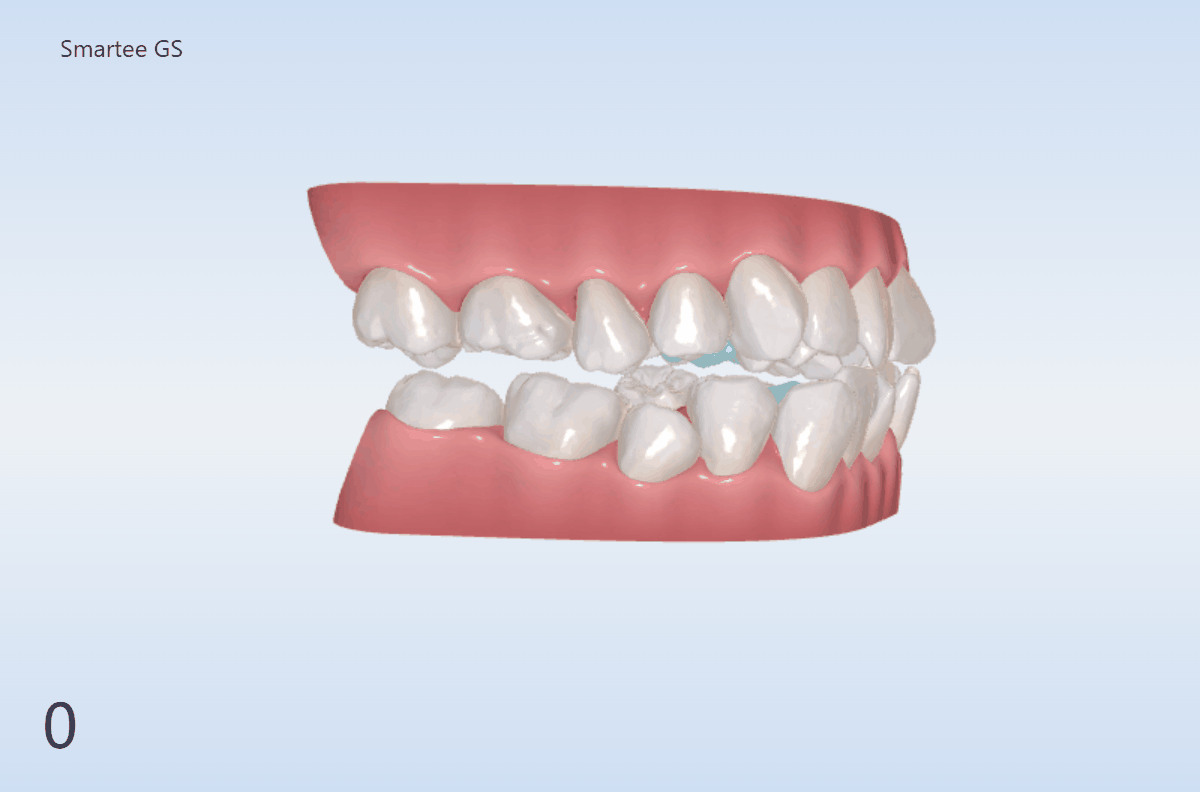

The Solution

顎の位置まで変える矯正治療

顎の位置が重要であっても、

従来の矯正ではそこまで踏み込めないケースが多くありました。

SmarteeGSは、

顎の位置から設計することで、

横顔そのものを整える矯正治療です。

歯並びだけでなく、骨格バランスまで考慮した治療設計